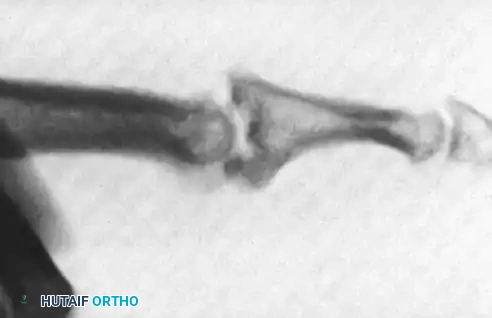

Figure 67-45A: Crush injury to the small finger resulting in a middle phalangeal fracture.

Figure 67-45B: AP radiograph demonstrating the inherently unstable nature of the fracture.

Figure 67-45C: Lateral radiograph confirming displacement requiring stabilization.

Figure 67-45D: Postoperative AP radiograph showing the Pratt technique of crossed Kirschner wire fixation providing excellent alignment.

Figure 67-45E: Postoperative lateral radiograph confirming concentric reduction and stability.